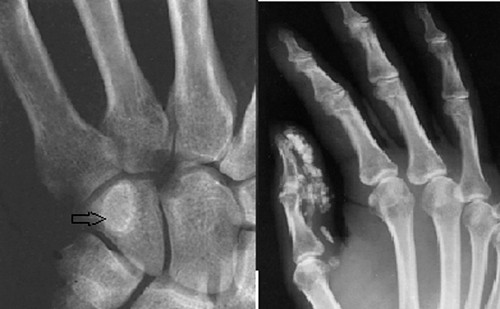

Sau hội chẩn, các bác sĩ Khoa Ngoại thần kinh - BV Đà Nẵng phẫu thuật gọt bỏ khối u xương ác tính và chọn giải pháp công nghệ in 3D, công nghệ hoàn toàn mới ở Việt Nam để thực hiện tái tạo lại bộ phận xương bị ăn mòn. Bệnh nhân được chụp CT vùng đầu, cả phần bị ăn mòn. Sau đó, bác sĩ sử dụng công nghệ mới để tái tạo xương, dập khuôn lưới titanium để thay thế phần xương bị mất, vừa đảm bảo thị lực và thẩm mỹ. Hiện bệnh nhân được theo dõi phục hồi tốt.